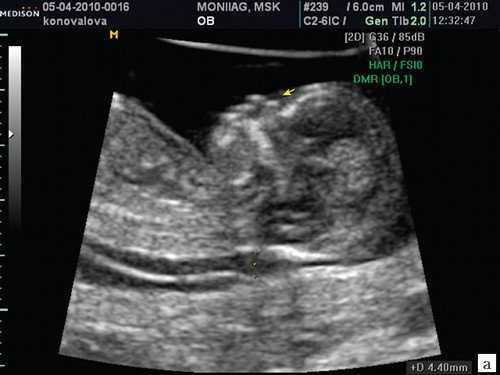

Считается, что носовая кость нормальна, когда она по своей структуре более эхогенна, чем надлежащая кожа и патологична, если она не видна (аплазия) (рис. 2) или ее длина меньше нормы (гипоплазия) (рис. 3). В случае одинаковой или меньшей эхогенности носовой кости чем кожи носовая кость считается патологической (рис. 4).

а) Носовая кость в 12 нед и 2 дня длиной 1,4 мм (меньше нижней границы нормы).

б) Носовая кость 2,1 мм в 14 нед у плода с синдромом Дауна.